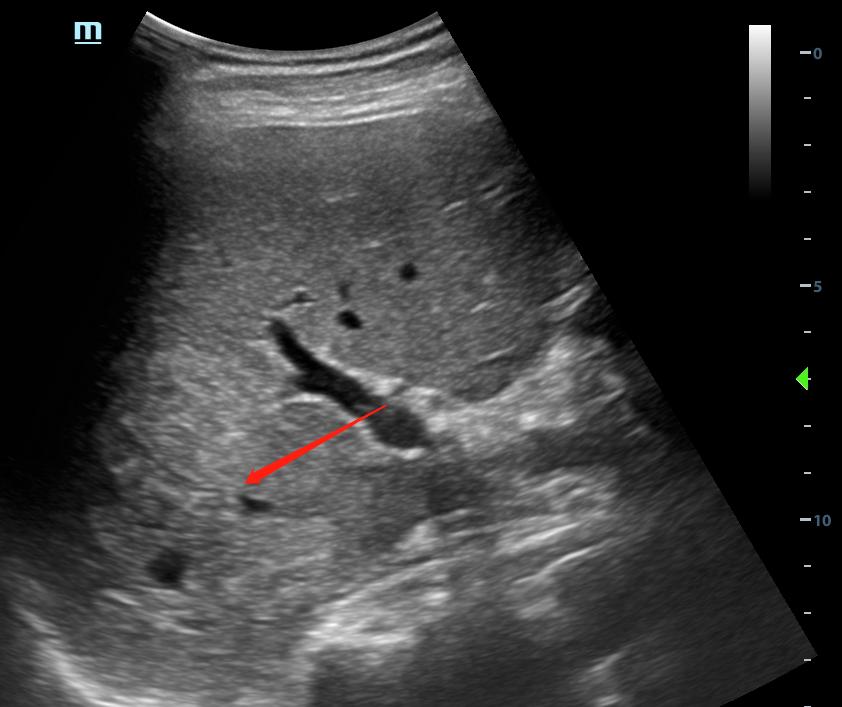

不同设备条件下得到的超声图像可能有很大差别,特别是肾脏血肿、肝脾挫伤。

对于外伤后患者,大量肾周血肿、明显的肝脾破裂谁都会看,但少量的肾脏血肿,隐匿性的肝肾挫伤或破裂,增益过高很可能就直接漏诊。

肝破裂

没有最合适的增益,只有反复调节的增益。

超声受气体、脂肪、组织密度等等等各种因素影响,同一台设备条件不一定适用所有人,每个患者都需要调节至显示清楚的条件。

对于同一个患者,不同增益下可能会给你带来不一样的信息,如果还有不会调节设备的小伙伴,可以阅读这里:0基础入门,超声设备的使用和调节